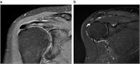

1. 急性の石灰沈着性滑液包炎は、腱板内に沈着した石灰が肩峰下滑液包へ流出して発生する結晶性滑液包炎である。突然発症する例が多い。

1. 腱板内に沈着した石灰が大きくなり、慢性化してインピンジメント症状や関節拘縮を引き起こすこともある。

1. 無症候性の石灰沈着症の発生率は人口の2.7~20%で、30~50歳に好発する。有症状の沈着症は50歳前後であり、女性(男女比は3:2)と棘上筋腱に多い。